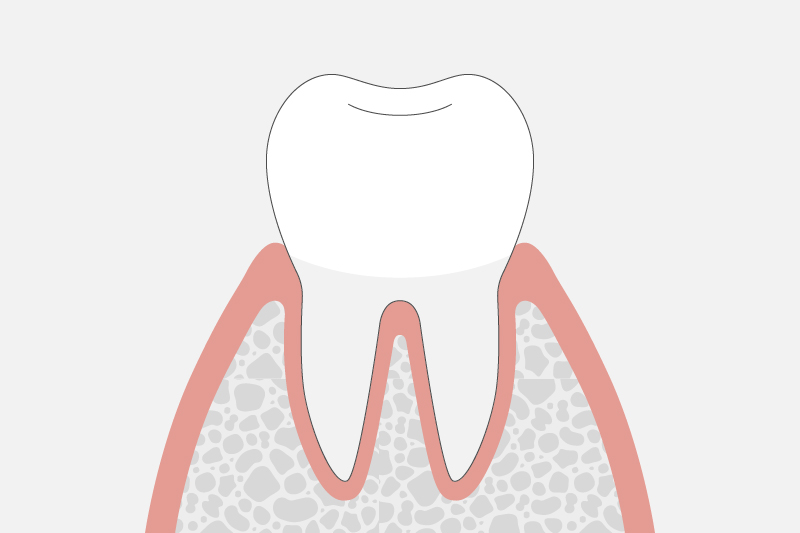

歯肉炎(歯周ポケットの深さ1〜2mm)

歯茎のみに炎症を引き起こしている状態です。

痛みといった自覚症状はほとんどありませんが、歯磨きの時や硬いものを食べた時に出血しやすくなる場合があります。